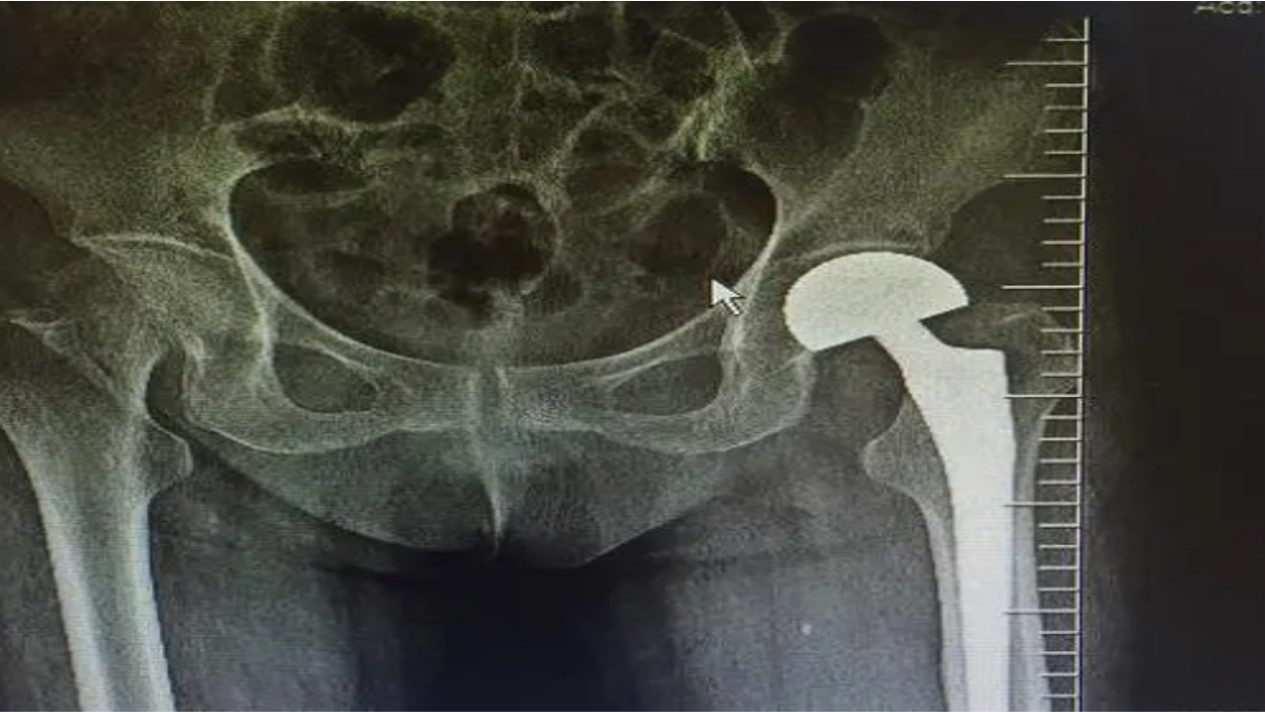

等送到医院,医生开了X线检查,结果显示“右股骨粗隆间骨折”。刘大爷听到“骨折”二字忙问医生:“摔骨折了,这么严重啊,这要多久才能好啊?”